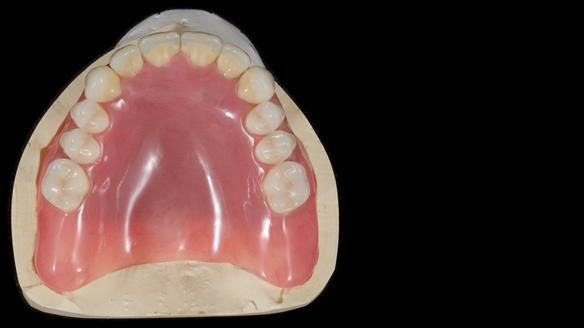

We provided her with an immediate upper denture (Mk 1), followed by a definitive metal-based upper denture (Mk 2). A lower removable partial denture was discussed, to be made only if needed once the upper treatment was complete. However, at review, this wasn’t necessary — Adnana had excellent neuromuscular control and function, even with a shortened dental arch (SDA).

Rowan, Sam Hesketh and Chris Hesketh provided the stunning technical work. I am very lucky to have them.

- Definitive denture (Mk 2), metal-based and custom-designed for her face

- A restored smile, restored lip support, and a patient who owned the journey